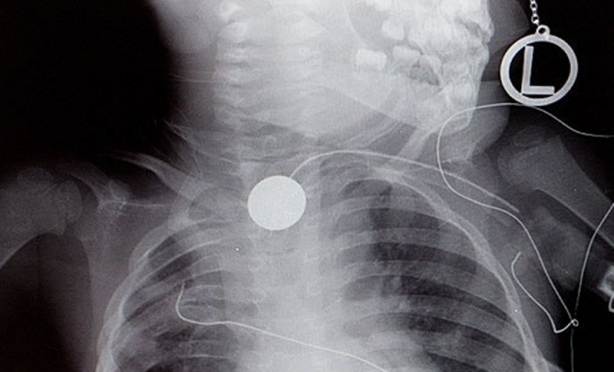

Yemek borusuna metal para sıkışmış bir çocuğun röntgeni...